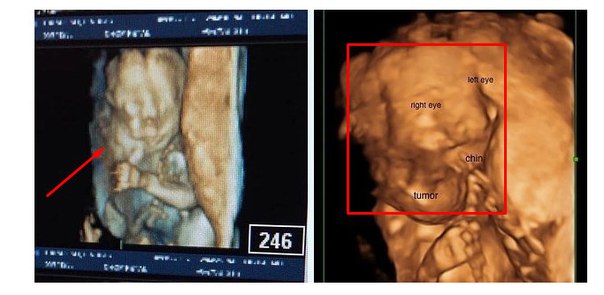

В конце 2015 года Линдси забеременела. Супруги жили в предвкушении скорого пополнения в семействе и даже выбрали будущей имя девочке — Омара. Однако их радость была недолгой на узи врачи обнаружили невероятное…